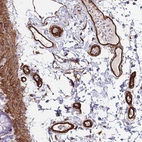

Immunohistochemical staining of human colon shows strong positivity in endothelial cells.